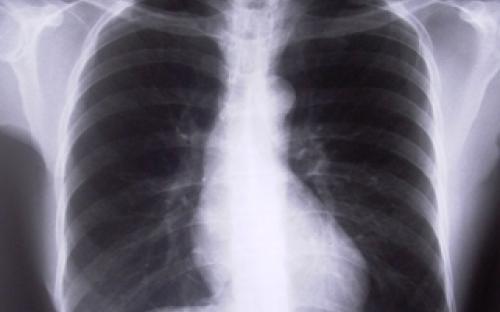

“วัณโรคดื้อยา” ปัญหาระดับชาติ